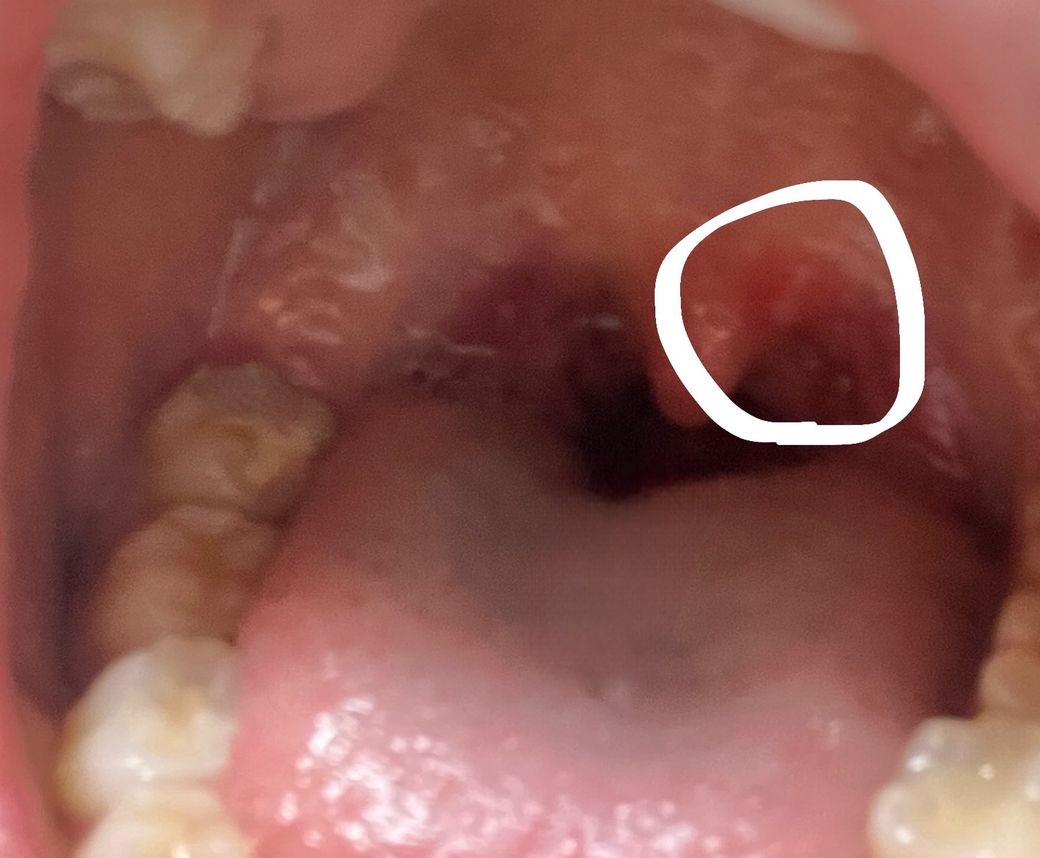

인후염?! 염증 궁금햐요ㅠㅠㅠ!!!

제가 목이 자주 부어서 병원에 가면 항상 의사 선생님이 인후염이라고 하셧는데

요번에는 사진처럼 한군데 염증도 낫어요!ㅜㅠㅠ

• 1번 째 사진

사진으로는 정확한 진단 불가능하며 병원 방문하셔서 직접 육안으로 진료 보셔야 합니다

올리신 사진 확인해보셨는지 모르겠지만 병변이 잘 안보여요

우선 헤르페스성 감염은 목에 염증을 일으킬 수 있지만, 보통 입 주변에 작은 수포 형태로 나타납니다. 따라서 단순히 목이 붓고 염증이 생겼다고 해서 헤르페스성 감염이라고 단정 짓기는 어렵습니다. 물론, 헤르페스 바이러스가 면역력이 약한 경우나 특수한 상황에서 목에 염증을 일으킬 수는 있지만, 일반적인 인후염은 바이러스나 세균 감염에 의한 경우가 더 흔해요

따라서 염증이 심한 경우나 고열, 발진이 동반된다면 병원에서 정확한 진단을 받는 것이 중요합니다. 의사 선생님께서 인후염이라고 진단하셨다면, 특별히 다른 원인보다는 일반적인 인후염일 가능성이 높습니다. 치료와 관리에 있어 바이러스성 인후염은 휴식과 수분 섭취로 회복할 수 있고, 세균성 인후염은 항생제 처방이 필요할 수 있습니다.